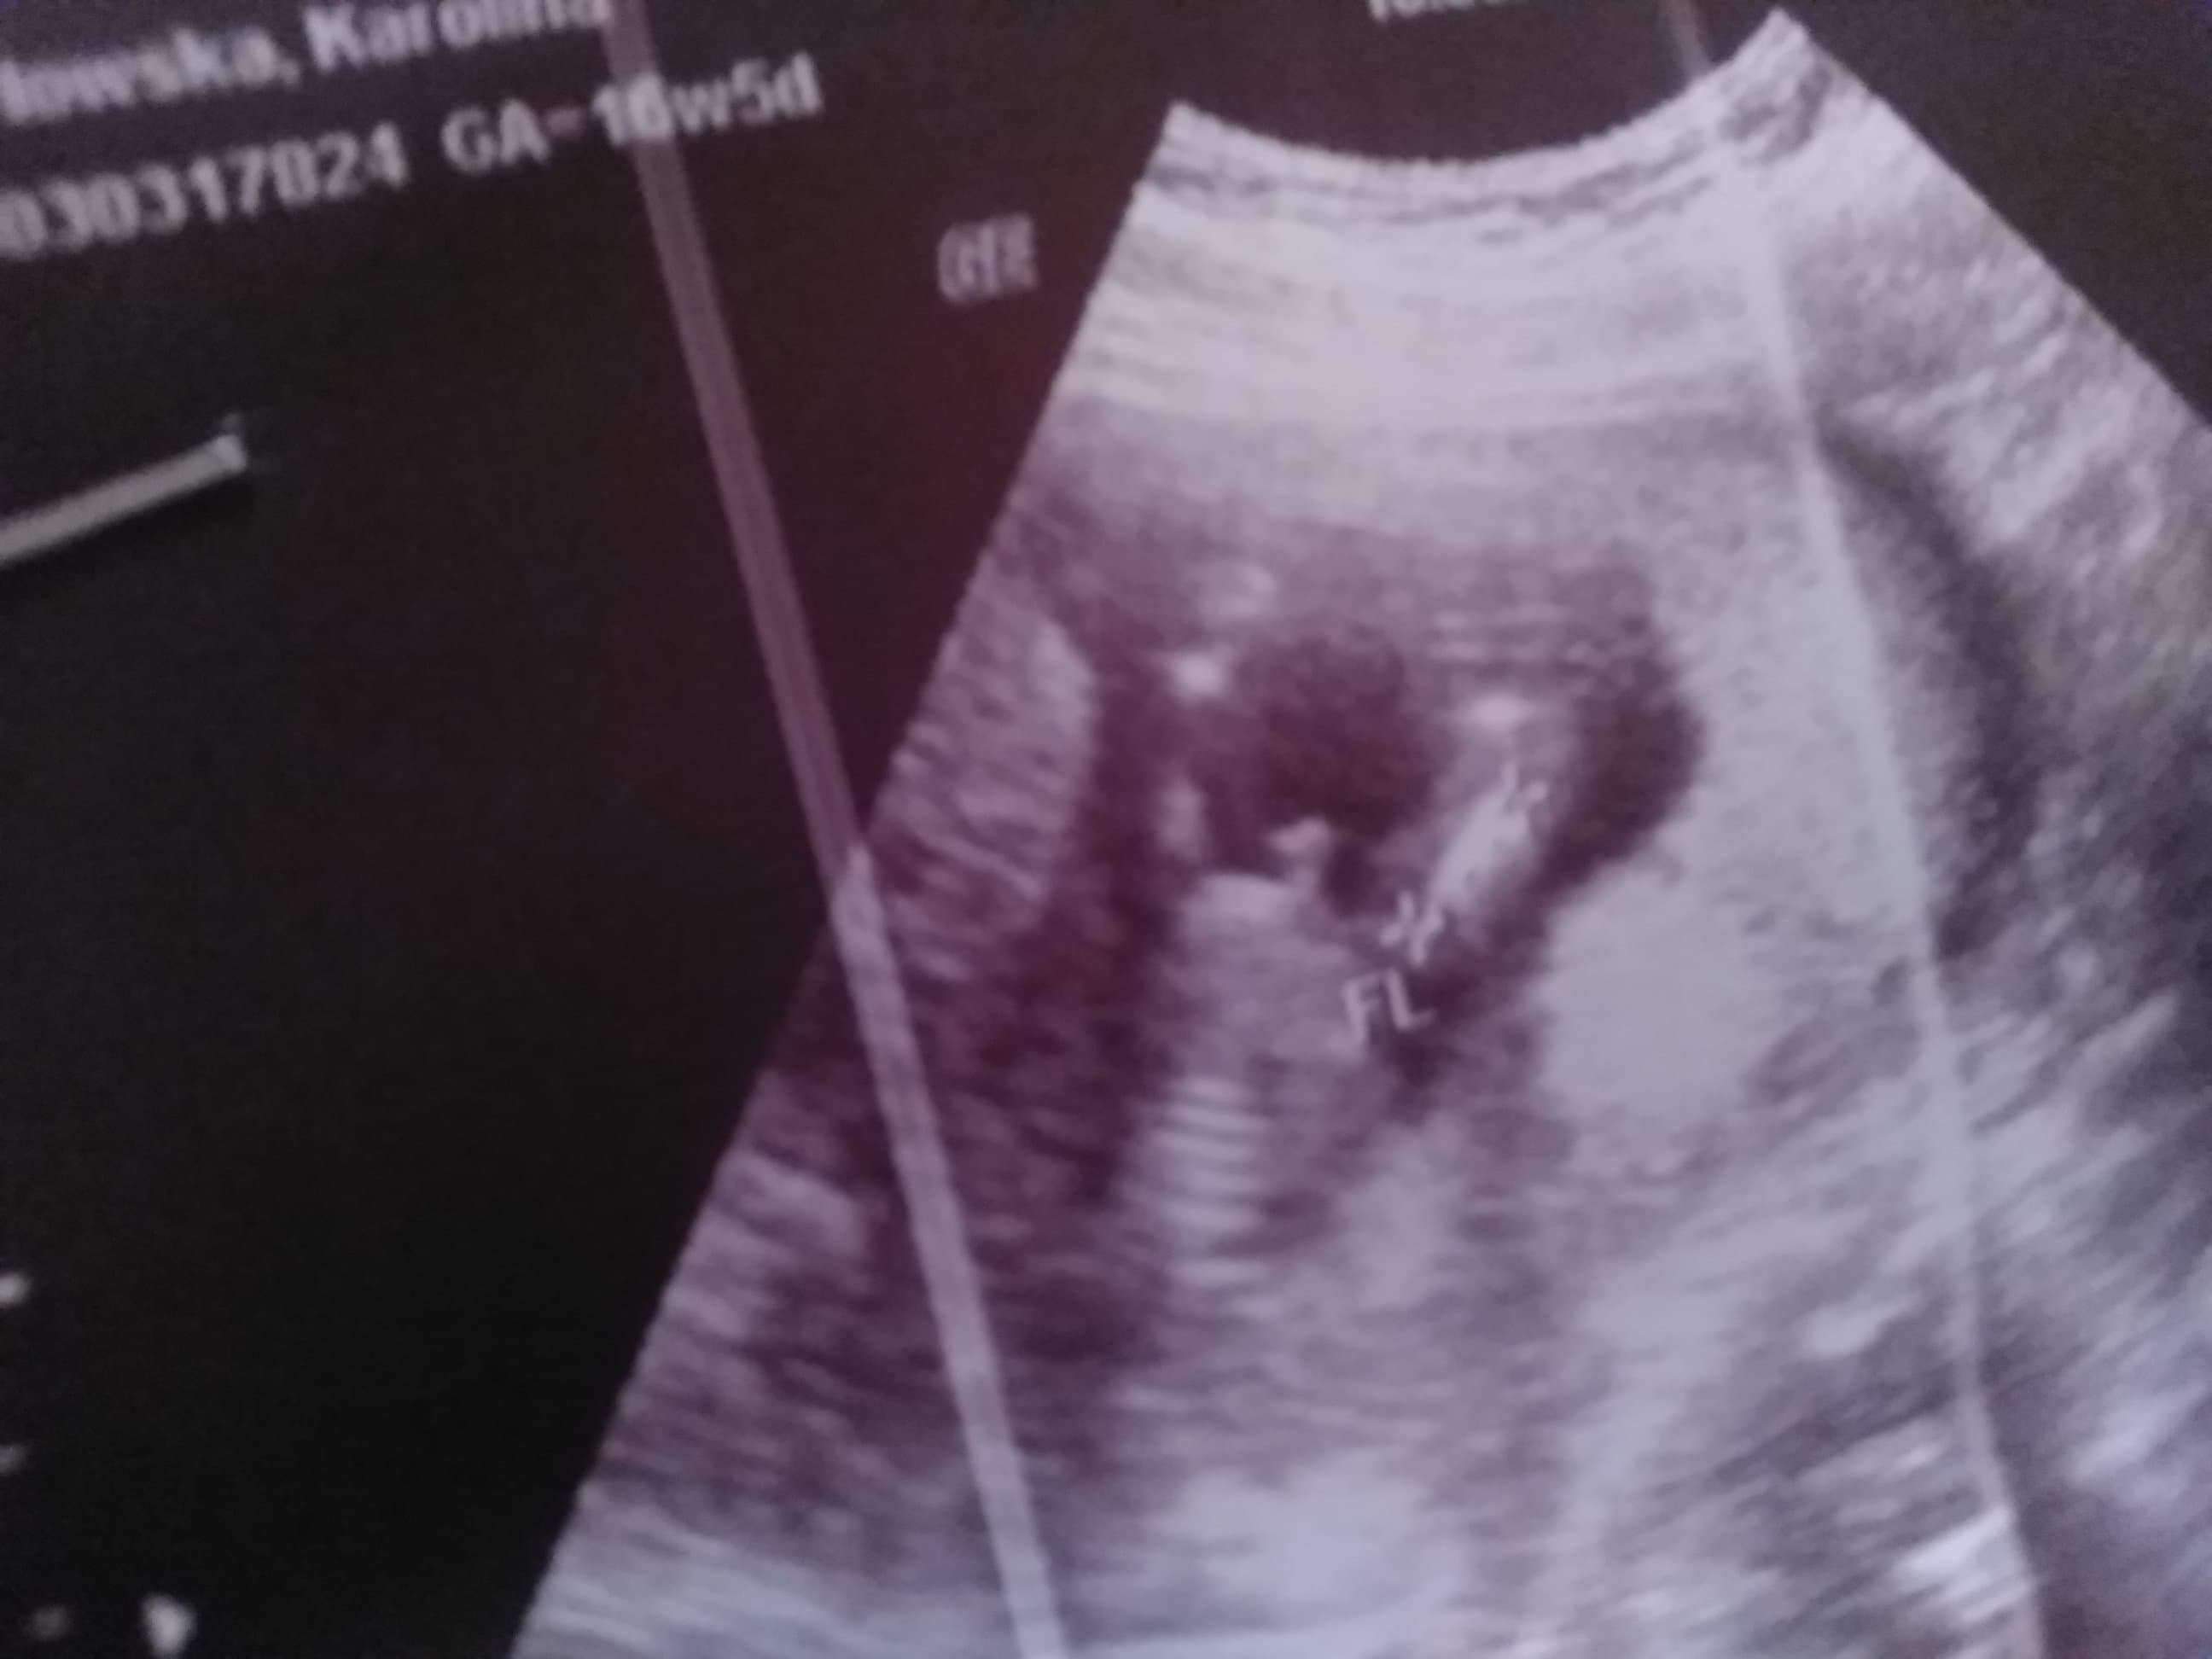

Usg chłopak czy dziewczynka

Witam w 19 tygodniu ciąży dowiedziałam się ze będę miała dziewczynkę w 20 tyg okazało się jednak , że to chłopak. Sama już nie wiem bo na jednym usg widać na pewno dziewuche a na drugim chłopca. Może to pempowina ?? Może ktoś mi pomoże rozwiązać ta zagadkę

Wedlug mnie bedziesz miala chlopca to zdjecie gdzie niby jest dzieeczynka nie wskazuje wcale na dziewczynke nie widac warg sromowych i lechtaczki slynnych 3 kresek.Poszukaj w google potty girl to zobaczysz o czym mowie.